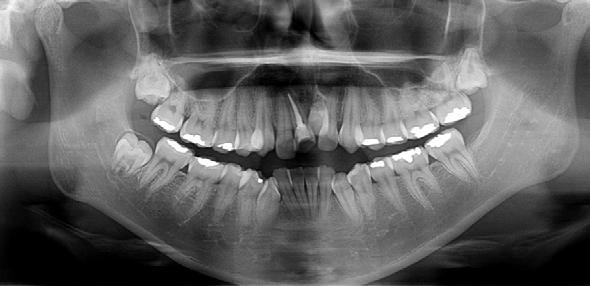

En la ortopantomografía se observó asimetría de las ramas mandibulares, reabsorción radicular severa del diente 21, extrusión de incisivos inferiores y presencia de los dientes 18, 28 y 48 (Figura 2 A). La radiografía lateral de cráneo nos permitió realizar el análisis cefalométrico de Ricketts en el cual se confirmó la clase II esqueletal, el biotipo dolicofacial y la retrusión mandibular (Figura 2 B y C y Tabla 1).

Figura 2. Radiografía ortopantomografía y lateral de cráneo.

En la ortopantomografía se puede apreciar el cierre de la mordida abierta anterior y la preservación de las longitudes radiculares en general (Figura 7A). En la radiografía lateral de cráneo y superposición final se puede observar la mejora general del perfil de la paciente y de sus inclinaciones dentales (Figura 7 B-D) (Tabla 1).